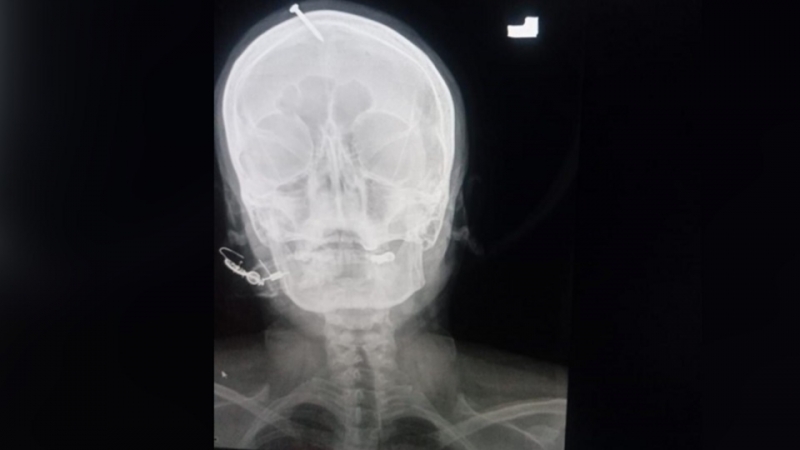

В Палестине женщина вбила гвоздь в голову по совету целителя для того, чтобы родить мальчика.

Гвоздь глубоко проник в череп женщины, домашние заметили "что-то не то", когда она потеряла сознание, пишет портал dawn.

"Они пытались удалить его дома, но не смогли", – сказал он, добавив, что врачи успешно удалили его после операции.